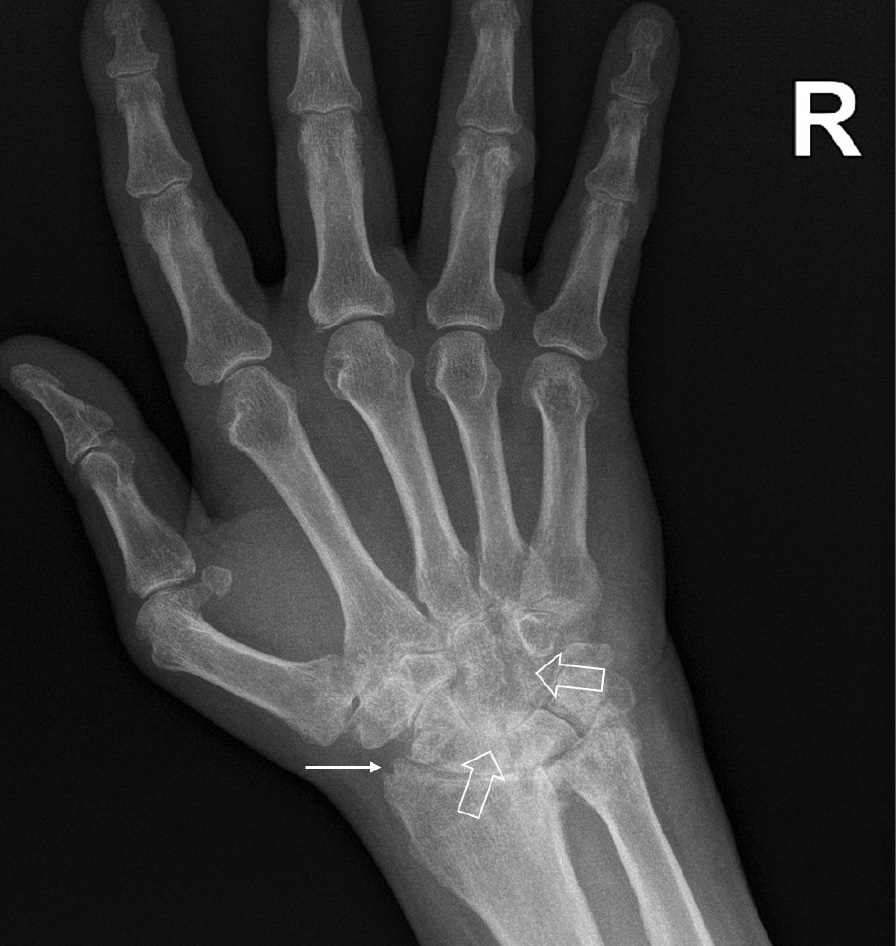

При компьютерной томографии органов грудной клетки данных за «свежие» очаговые и инфильтративные изменения не получено. Увеличения лимфатических узлов подмышечных областей, средостения, корней легких не выявлено. Отмечался усиленный грудной кифоз, обызвествление передней продольной связки, на всем уровне исследования определялись передне-боковые спондилофиты, а также анкилоз большинства реберно-поперечных суставов. По данным рентгенографии кистей (рис. 1, 2) и стоп (рис. 3, 4) диагностированы признаки эрозивного артрита, анкилоз суставов запястья. По данным МРТ крестцово-подвздошных суставов (КПС) определялся неравномерный анкилоз КПС, хрящи по суставным поверхностям неравномерной толщины, примерно на половине протяжении сустава отсутствуют, «суставной промежуток» облитерирован. Неравномерность и нечеткость контура суставных поверхностей за счет множества краевых эрозий справа, единичных – слева, с наличием остеокластоза, в нижнем отделе слева по смежным отделам определяются участки трабекулярного отека, данная находка клинически интерпретирована как двусторонний активный сакроилиит (рис. 5, 6).

Рис. 6. Магнитно-резонансная томография (Т1-взвешенное изображение в косой корональной проекции). Протяженные участки анкилоза крестцово-подвздошных суставов (толстые стрелки), субхондральная киста правой латеральной массы крестца (тонкая стрелка). При магнитно-резонансной томографии крестцово-подвздошных сочленений с обеих сторон определяются крупные зоны анкилоза (суставные щели полностью облитерированы на 1/3 поверхности сустава справа, на 2/3 поверхности слева, что соответствует III рентгенологической стадии сакроилиита справа, IV стадии слева по Келлгрену). На остальных участках суставной хрящ неравномерно истончен, суставные поверхности неровные за счет множественных эрозий справа, единичных – слева. Определяются единичные мелкие (4 мм) субхондральные кисты справа

Ведущим диагнозом в течение всей истории заболевания был «анкилозирующий спондилоартрит, смешанная форма, HLA-B27-ассоциированный», поставленный на основании типичного поражения позвоночника с формированием деформаций (костный анкилоз в переднем отделе Th4 и Th7, множественные синдесмофиты в области передних углов тел позвонков). Заключение МРТ КПС типично для пациента с АС: двусторонний анкилоз КПС, множественные краевые эрозии, с наличием остеокластоза и признаками трабекулярного отека костной ткани, двусторонний сакроилиит. Клиническая картина, проявляющаяся болями воспалительного характера и скованностью в пояснично-крестцовом отделе позвоночника, нарушением объема движения в позвоночнике, была характерна для прогрессирования АС. Диагноз подтверждался наличием положительного гена HLA-B27 [2].